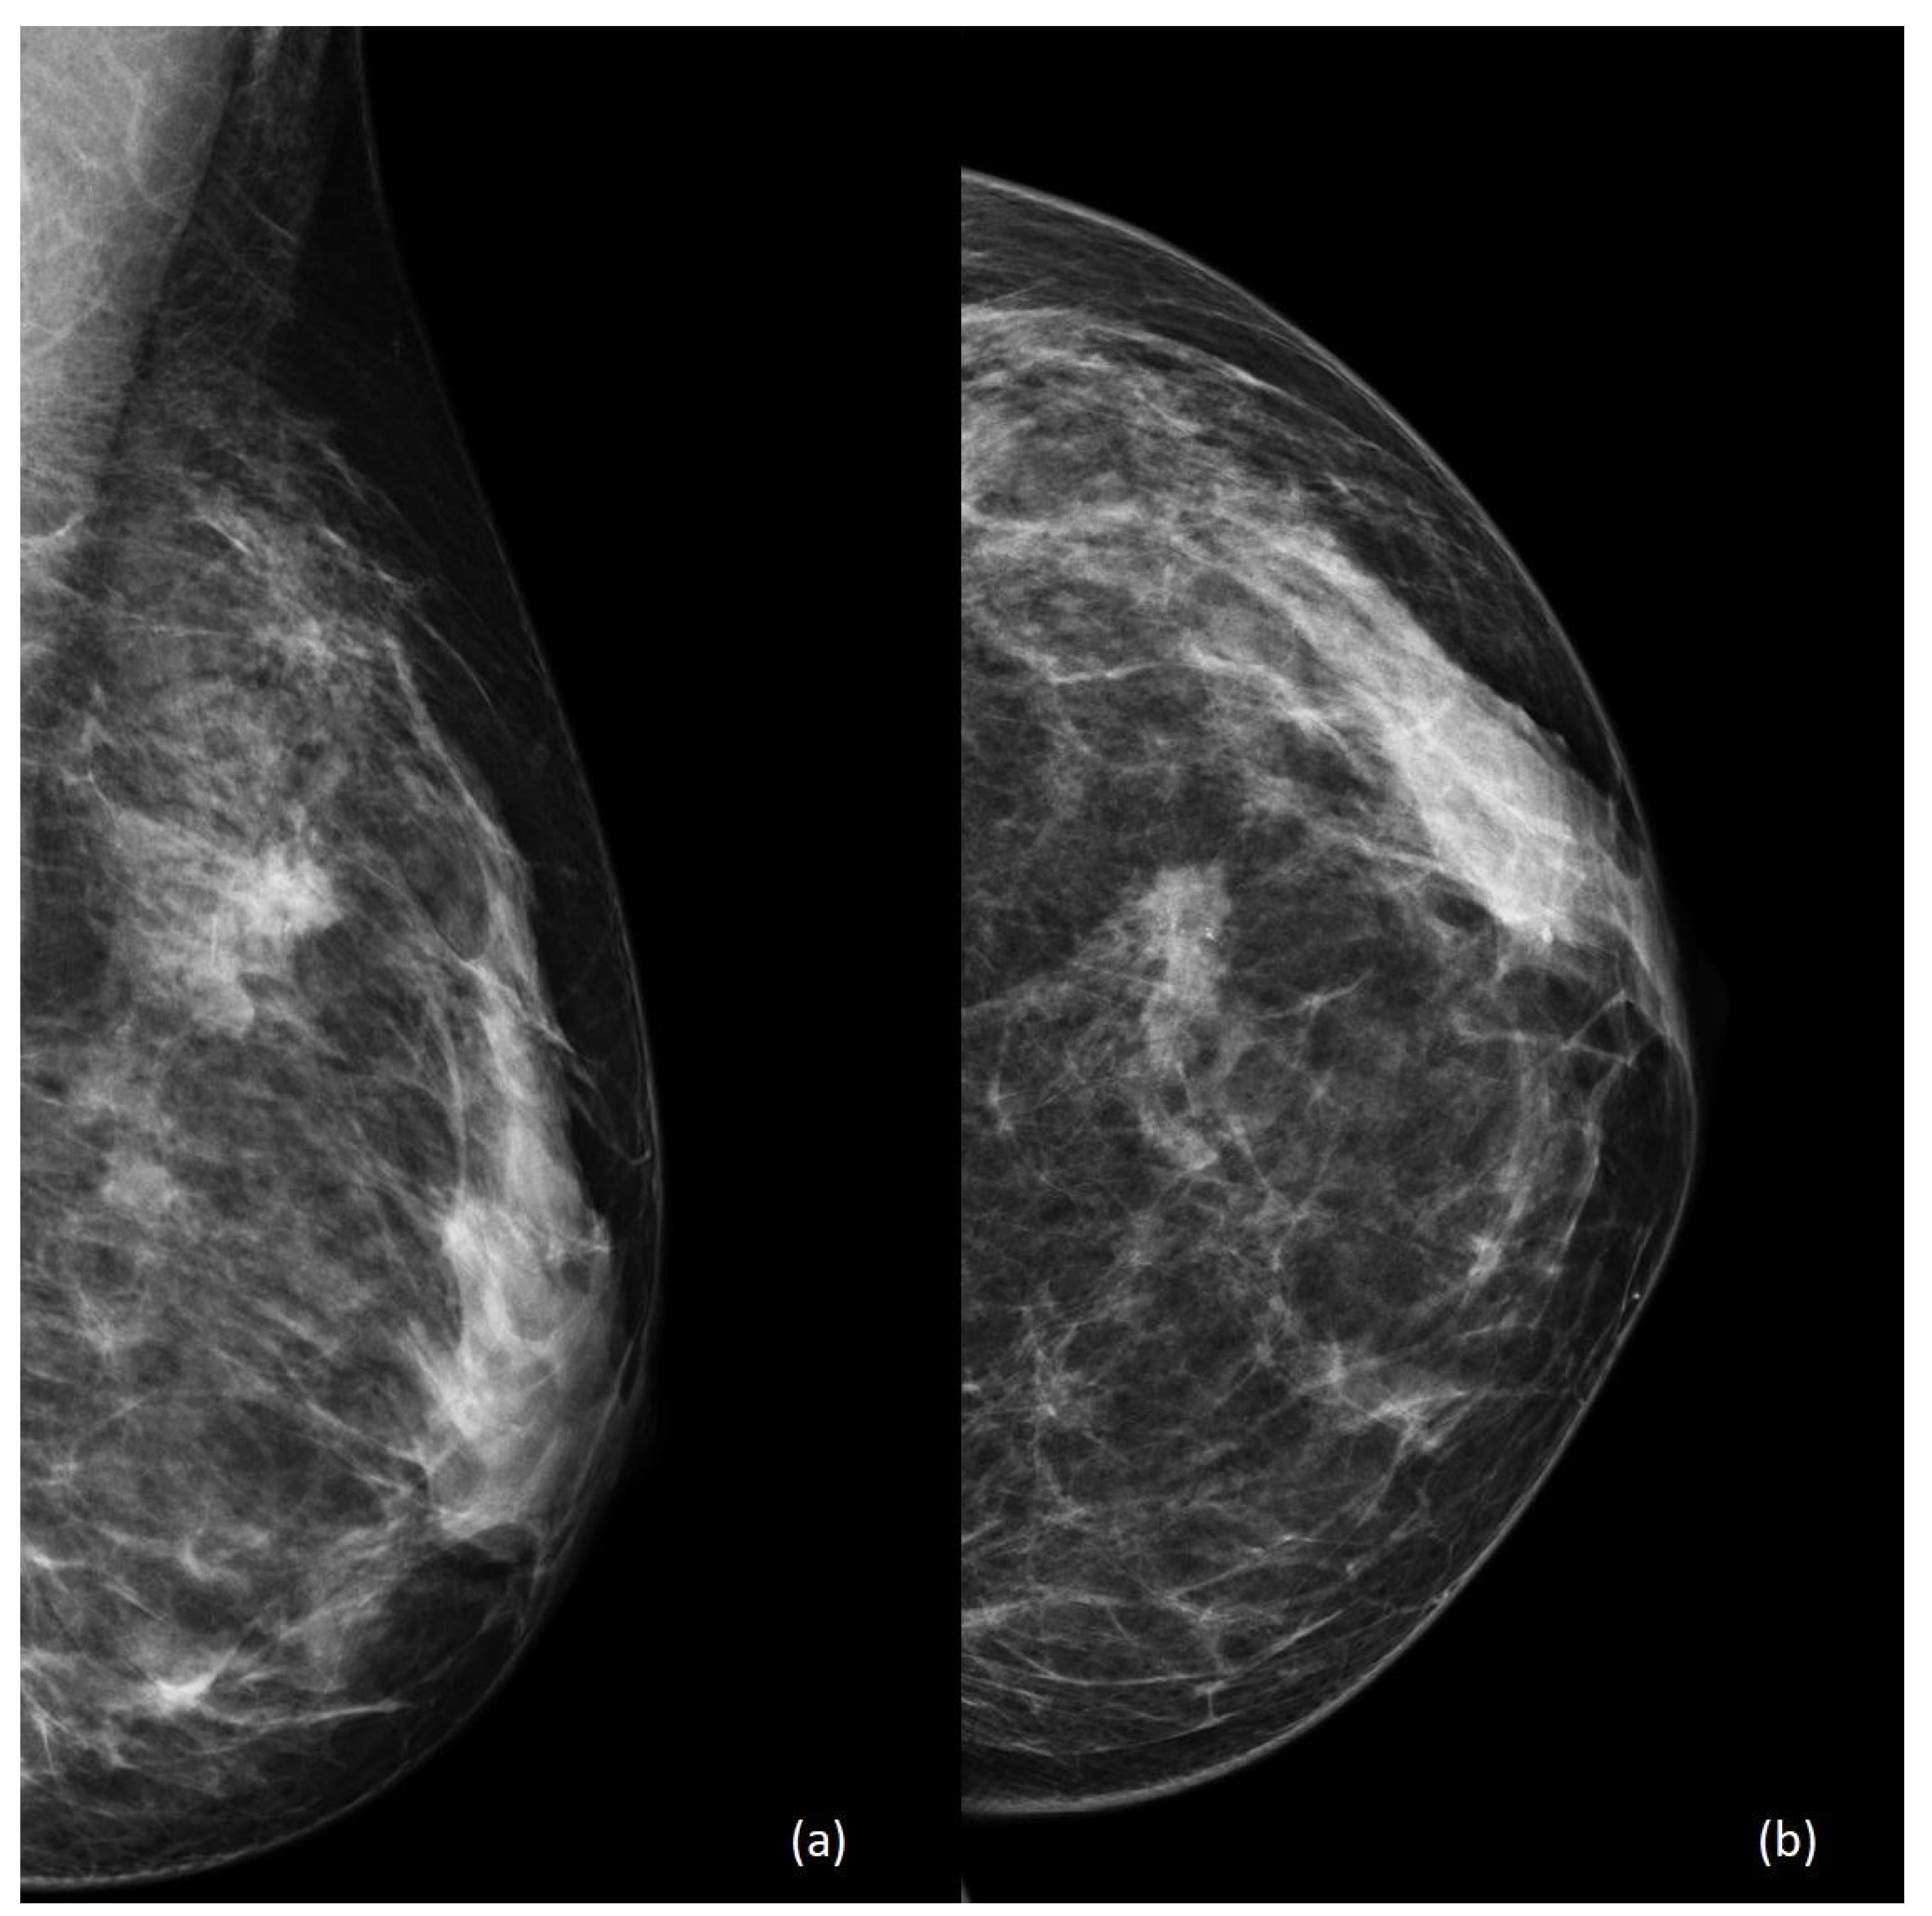

4. Imaging

- Ayyappan, A.P.; Kulkarni, S.; Crystal, P. Pregnancy-associated breast cancer: Spectrum of imaging appearances. Br. J. Radiol. 2010, 83, 529–534. [Google Scholar] [CrossRef] [PubMed]

- Wanders, J.O.; Holland, K.; Veldhuis, W.B.; Mann, R.M.; Pijnappel, R.M.; Peeters, P.H.; van Gils, C.H.; Karssemeijer, N. Volumetric breast density affects performance of digital screening mammography. Breast Cancer Res. Treat. 2017, 162, 95–103. [Google Scholar] [CrossRef] [PubMed]